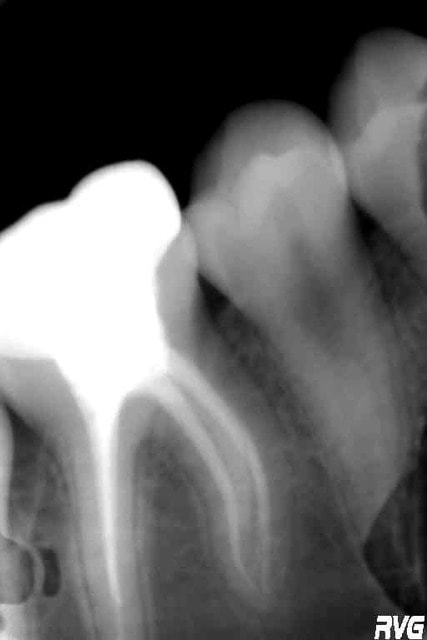

J'ai fait cette couronne sur une fillette de 9 ans. La radio est prise 3 ans après, il y a eu un accident de descellement (faible hauteur coronaire).

Il faudra bien sûr la refaire, mais si possible pas avant la fin de la croissance et du ttt orthodontique.

A noter que les CPP (coiffes pédo préformées pour dents permanentes) peuvent-être indiquées, mais il faut acheter le coffret.

Bien sûr il faut évaluer le pronostic (délabrement, endo, odf), et c'est sans doute ça le plus difficile. Dans le cas de cette patiente, le risque carieux global était faible (aucune carie sur les dents lactéales), mais fragilité ++ de cette 46 pour cause de MIH, atteinte bcp plus modérée des trois autres dents de 6 ans.